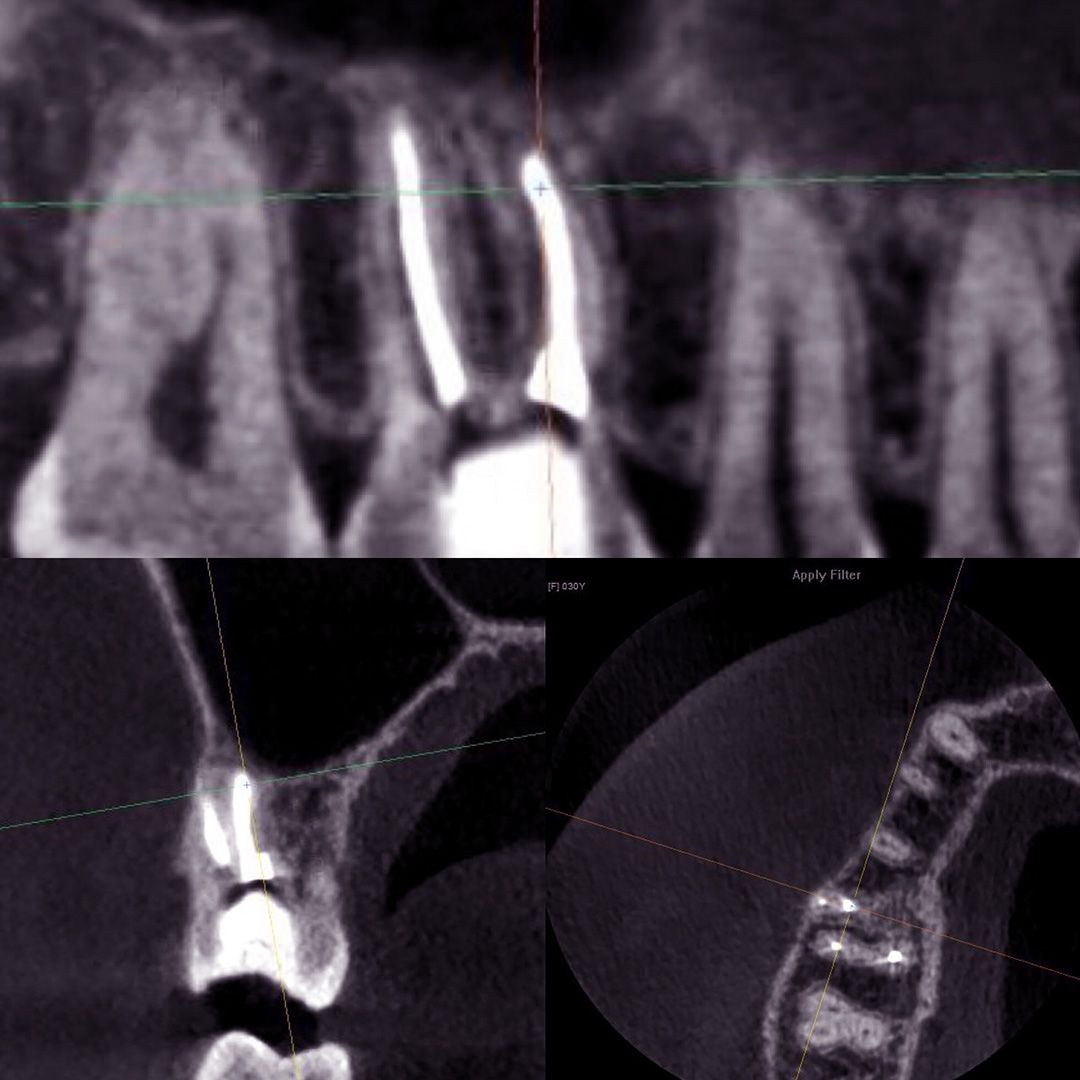

Пациентка после лечения в другой клинике обратилась в «Стоматологию Комфорта» с жалобами на ноющие боли в области жевательных зубов верхней челюсти. Боли усиливались при принятии пищи и горячих напитков. В результате проведения конусно-лучевой компьютерной томографии врач Вахлюева Елена Сергеевна обнаружила пропущенный дополнительный канал в ранее леченом моляре. Проведено селективное эндодонтическое лечение с пломбированием зуба.

- проведение конусно-лучевой компьютерной томографии и выявление проблемы;

- селективное эндодонтическое лечение зуба 1.6;

- пломбирование канала зуба.